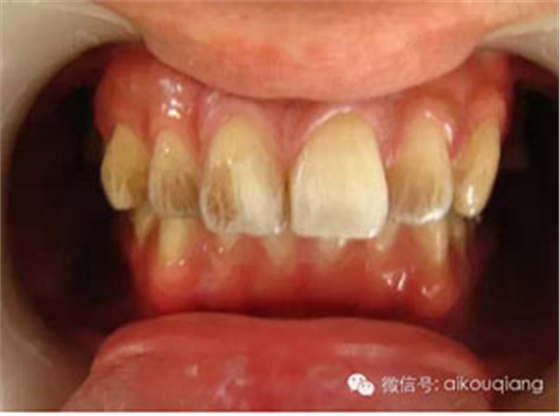

定期洗牙是目前最有效的治療牙周疾病的方式。下面是洗牙前后的對(duì)比圖:

潔牙噴砂槍?zhuān)p松把牙齒表面的色素、茶質(zhì)等去除

男性成年人喜歡喝茶、抽煙,造成牙齒表面色素沉著,很不美觀

洗牙(潔治)后,潔白如一